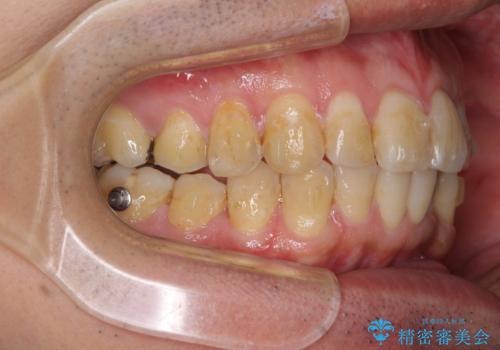

前歯のデコボコと下顎の八重歯 インビザラインによる矯正治療

- 前歯のデコボコや八重歯を気にして来院された患者様です。

インビザラインを用いて、歯列を整えることとしました。

下顎前歯は後戻りを起こしやすいため、舌側を細いワイヤーで固定し、マウスピース型リテーナーで保定を行うこととしました。